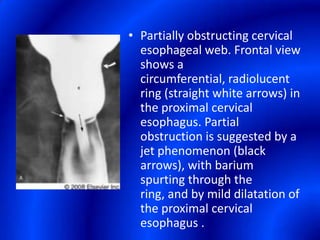

This document provides information about a barium swallow procedure. It begins with an introduction and overview of the embryology and anatomy of the pharynx and esophagus. It then describes the procedure itself, including preparation, technique, views obtained, and indications. Specific conditions that may be examined include pharyngeal and esophageal webs, foreign body impaction, scleroderma, dysphagia, mediastinal masses, and carcinoma. Diagrams are provided to illustrate normal anatomy and various pathological findings.